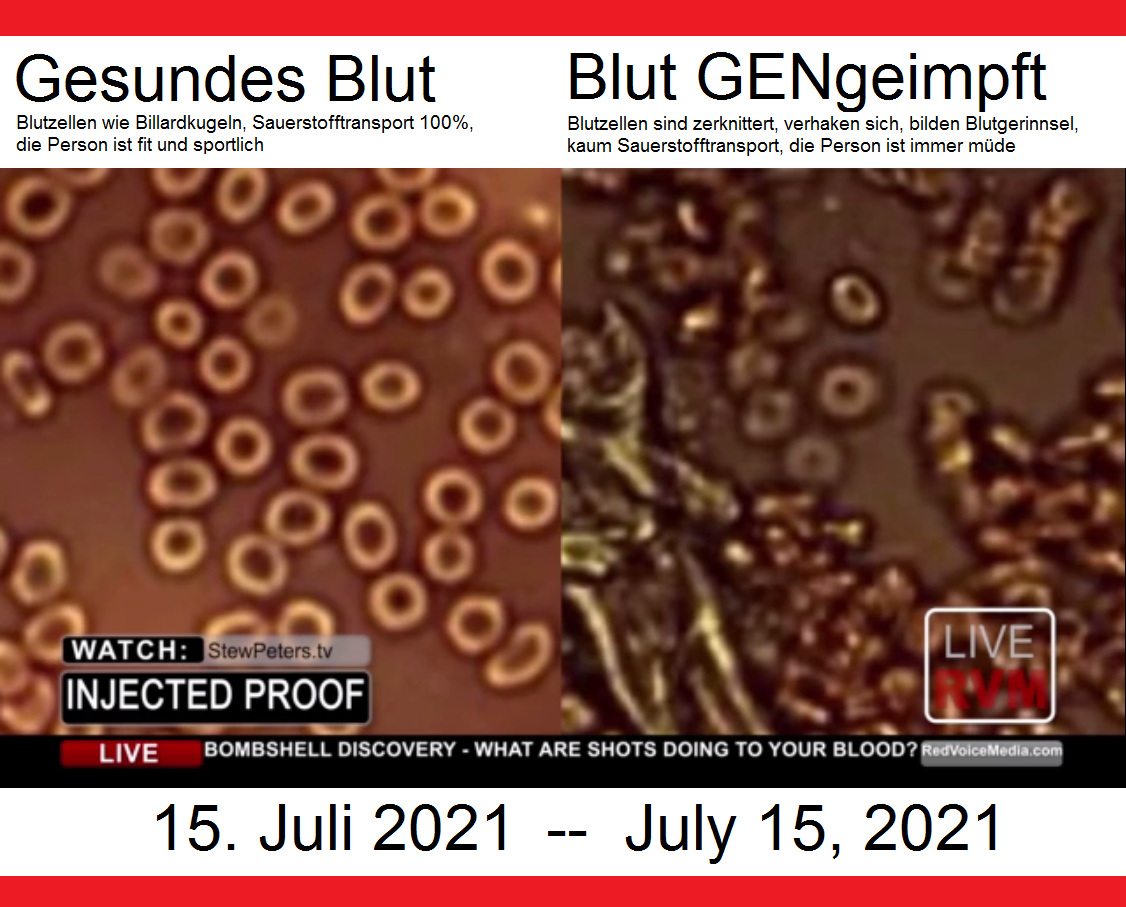

15.7.2021:

Medizinisches: Blutbild von GENgeimpften:

Video 15.7.2021: Bombshell discovery -

what are shots doing to your blood?

https://rumble.com/vjw5kq-breaking-discovery-what-covid-injections-do-to-your-blood-doctor-releases-h.html

Das Video ist auch auf Bitchute:

Video

15.7.2021: Vergleich Blutbild

gesund-GENgeimpft - comparison blood

healthy-vaccinated (11'51'')

15.7.2021: Vergleich Blutbild

gesund-GENgeimpft - comparison blood

healthy-vaccinated (11'51'')

https://www.bitchute.com/video/DW5aZQCK8YBc/

- Bitchute-Kanal: NatMed-etc. -

hochgeladen am 27.9.2021

Beim gesunden Blut (links) sind die Blutzellen wie

Billardkugeln und der Sauerstofftransport ist 100%,

die Person ist sportlich fit. Link:

https://www.bitchute.com/video/DW5aZQCK8YBc/ - Die

Blutzellen der GENgeimpften sind zerknittert,

verhaken sich, provozieren Blutgerinnsel+Thrombosen.

UND: Sauerstofftransport ist kaum noch möglich,

Dauermüdigkeit, weil alle Organe unterversorgt sind.

DER FOTOBEWEIS: Die Spritzen, die da als "Impfungen"

bezeichnet werden, sind absolut giftig, und der

Beweis ist nun erbracht!

PHOTOGRAPHIC PROOF! The shots being referred to as

'vaccines' are absolutely poisonous, and the proof

is now here!

With healthy blood (left) the blood cells are like

billard balls and there is full 100% oxygen

transport, so the person is sportive and fit. The

blood cells of GENE vaccinated are crumpled, they

stick together forming clots and thromboses. AND:

oxygen transport is hardly possibble, eternal

tiredness comes up because all organs suffer lack of

oxygen.

www.StewPeters.tv | www.DrJaneRuby.com

Quelle / Source: Video auf Rumble:

https://rumble.com/vjw5kq-breaking-discovery-what-covid-injections-do-to-your-blood-doctor-releases-h.html